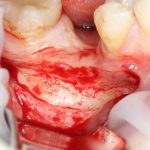

6. Фиксация перемещенного фрагмента.

Сделать это можно по-разному.

Наиболее простой вариант — с помощью графта. Есть у вас есть графт в виде твердого блока, то можно просто «расклинить» им альвеолярный гребень — и этого будет почти достаточно. «Почти» — потому, что, практически, любой графт даёт усадку, следовательно, со временем, перемещенный фрагмент станет подвижным. Это не наш вариант.

При вертикальной остеотомии очень удобно использовать длинные винты. Так, как указано на схеме.

Кроме того, с помощью винтов можно «прецизионно» зафиксировать костный фрагмент, передвигая его как на домкрате:

При горизонтальной остеотомии, на мой взгляд, удобнее использовать минипластины. Как я уже отмечал выше, в практике мы используем X- и H-образные минипластины под винты размером 0.9х4мм. Количество металла в разных условиях может быть разным — всё зависит от того, на каком этапе достигается полная неподвижность перемещенного костного фрагмента.